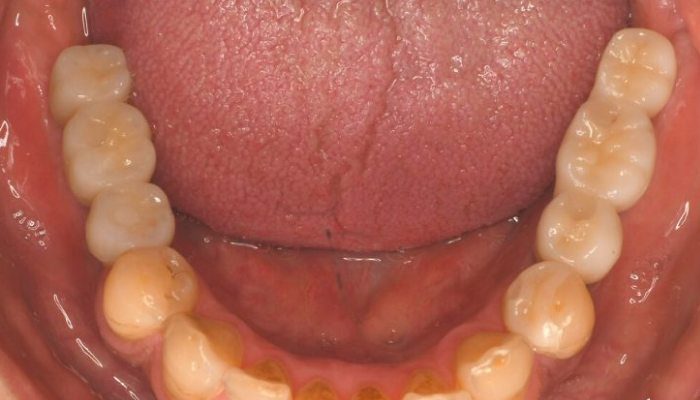

多くの歯を失う複数の歯が失われることで、噛み合わせが大きく乱れます。これにより咀嚼機能が著しく低下し、食事が困難になるだけでなく、顎関節への負担や筋肉の不調などが発生しやすくなります。最終的には多くの歯が失われ、入れ歯やインプラントなどの包括的な治療が必要になる場合があります。

全顎治療(お口全体の治療)

多くの歯科医院では、虫歯1本を治療して終了するケースが一般的です。しかし、噛み合わせの機能はお口の中すべての歯がそろってこそ正常に保たれるものです。たった1本の歯が欠けたり、傾いたり、抜けたりすると、顎の位置が狂い、全体のバランスに悪影響を及ぼします。そのため、歯1本の治療であっても、噛み合わせ全体を考慮することが非常に重要です。全顎的に噛み合わせを診る歯科医院は多くないため、選択肢の一つとして全顎治療(お口全体の治療)をお考えください。